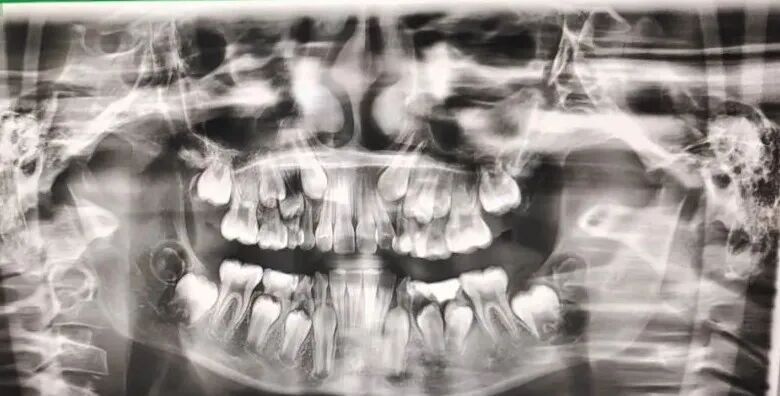

CBCT是目前国际最先进的口腔科专用CT,在业界被誉为神奇的"慧眼",具有扫描快、范围大、精度高、应用广、放射剂量极低的特点。可以通过其强大的处理软件功能以及面部匹配技术迅速形成清晰逼真的三维图像,在智齿拔除、牙种植测量、多生牙定位、颞下颌关节疾病、颌骨三维重建、根管治疗评估、正畸设计等方面提供精准的诊断与治疗依据。

5.8类拍摄模式:成人全景、儿童全景、前齿拍摄、左侧拍摄、右侧拍摄、TMJ张口、TMJ闭口、上颌窦。